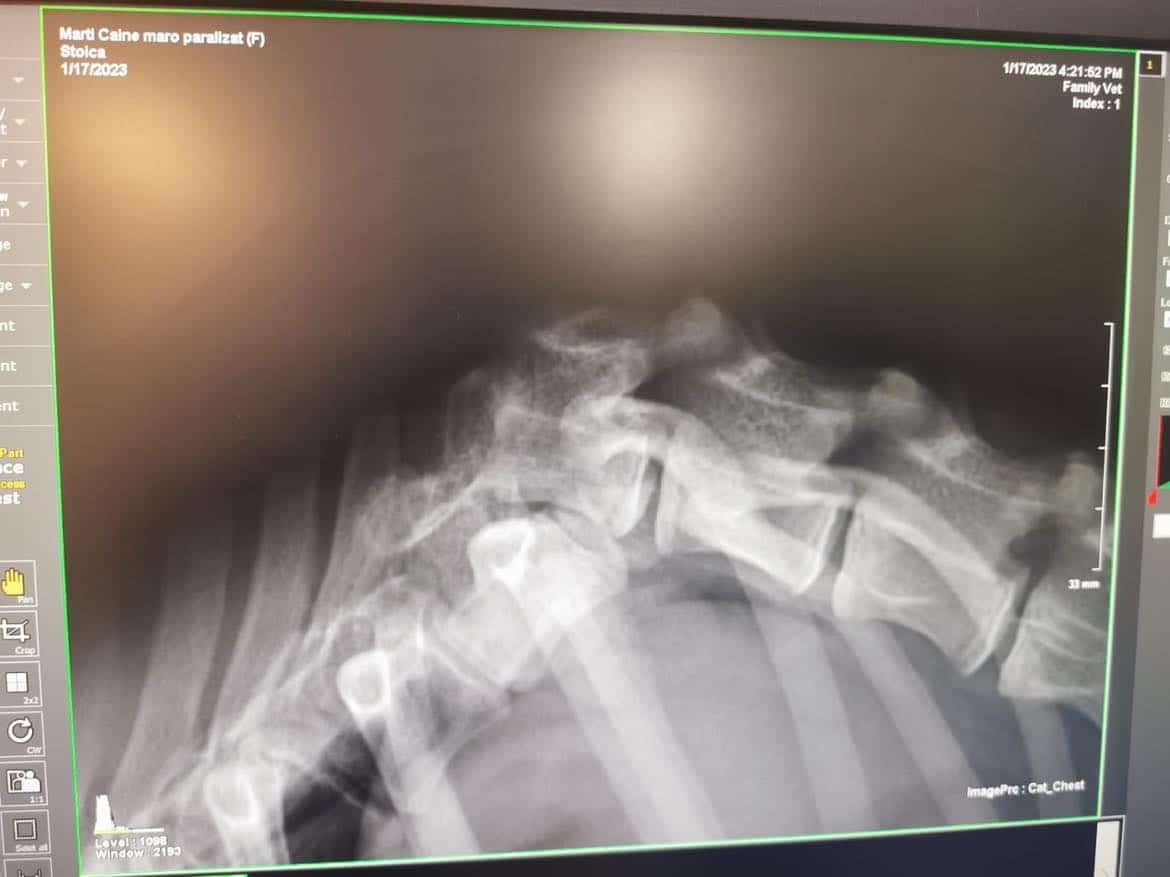

02/23 Zümra war in der Klinik und wurde geröngt, leider kann man in Rumänien für sie nicht mehr viel tun. Sie hat eine gebrochene Wirbelsäule. Wir versuchen nun erst einmal ein paar Übungen vor Ort und müssen schauen, ob sich etwas verbessert.